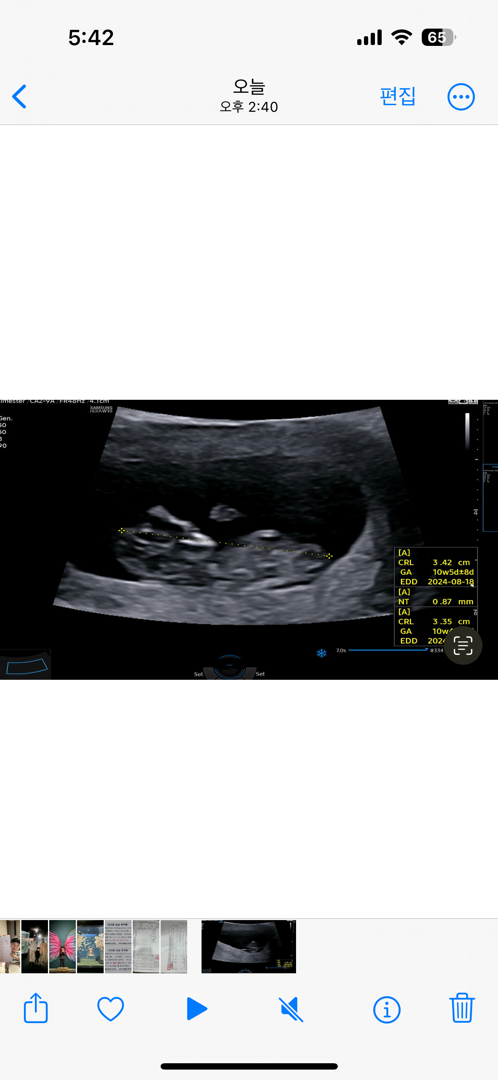

10주5일이네요ㅎㅎ 시간은 정말 빠른 거 같아요! 혹시 각도 구별 가능하신 분 계실까요????